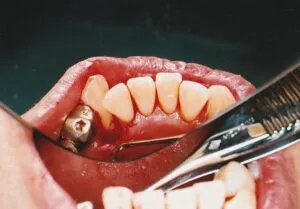

カルテに古い写真が貼ってあって、、昔は全部フィルム写真にとって記録を残していました。大部分は処分したのですが、なんと

平成13年のものが残っていました。昔は歯周病の手術もたまにやっていました。

最近はメンテナンスがしっかりと出来るようになったのと皆さんしっかりと歯を磨くようになったのでひどい歯周病の方が減って、

手術をほとんどやらなくなってしまいました。患者さんにとっては良い

傾向だと思います